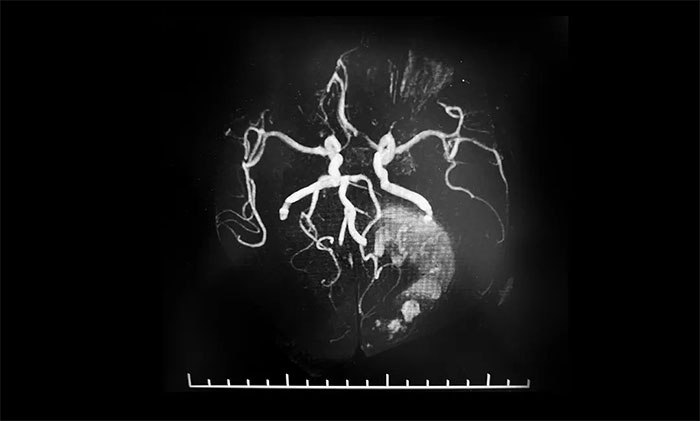

▲ 術前MRA,瞭解腫瘤供血情況

術前,潘仁龍主任給予患者脱水劑、白蛋白、甘露醇等藥物治療,患者病情逐漸穩定,可以睜眼,身體相關指標達到手術條件。為了進一步降低手術風險,李士其教授等專家團隊進行了詳細的術前準備,包括手術設計、切口大小設計、手術備血等。同時,術前進行了磁共振血管成像,詳細瞭解腫瘤供血情況,確保手術可控,萬無一失。